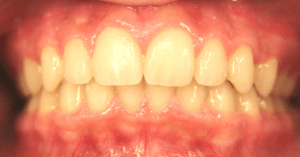

Open Bite

An open bite occurs when there is insufficient vertical overlap of the teeth. It is caused by oral habits such as a tongue thrust, thumb or finger sucking or when the jaws don’t grow evenly. Timing of treatment is critical to the overall success of the therapy.

Before and After Photos: Open Bite Correction